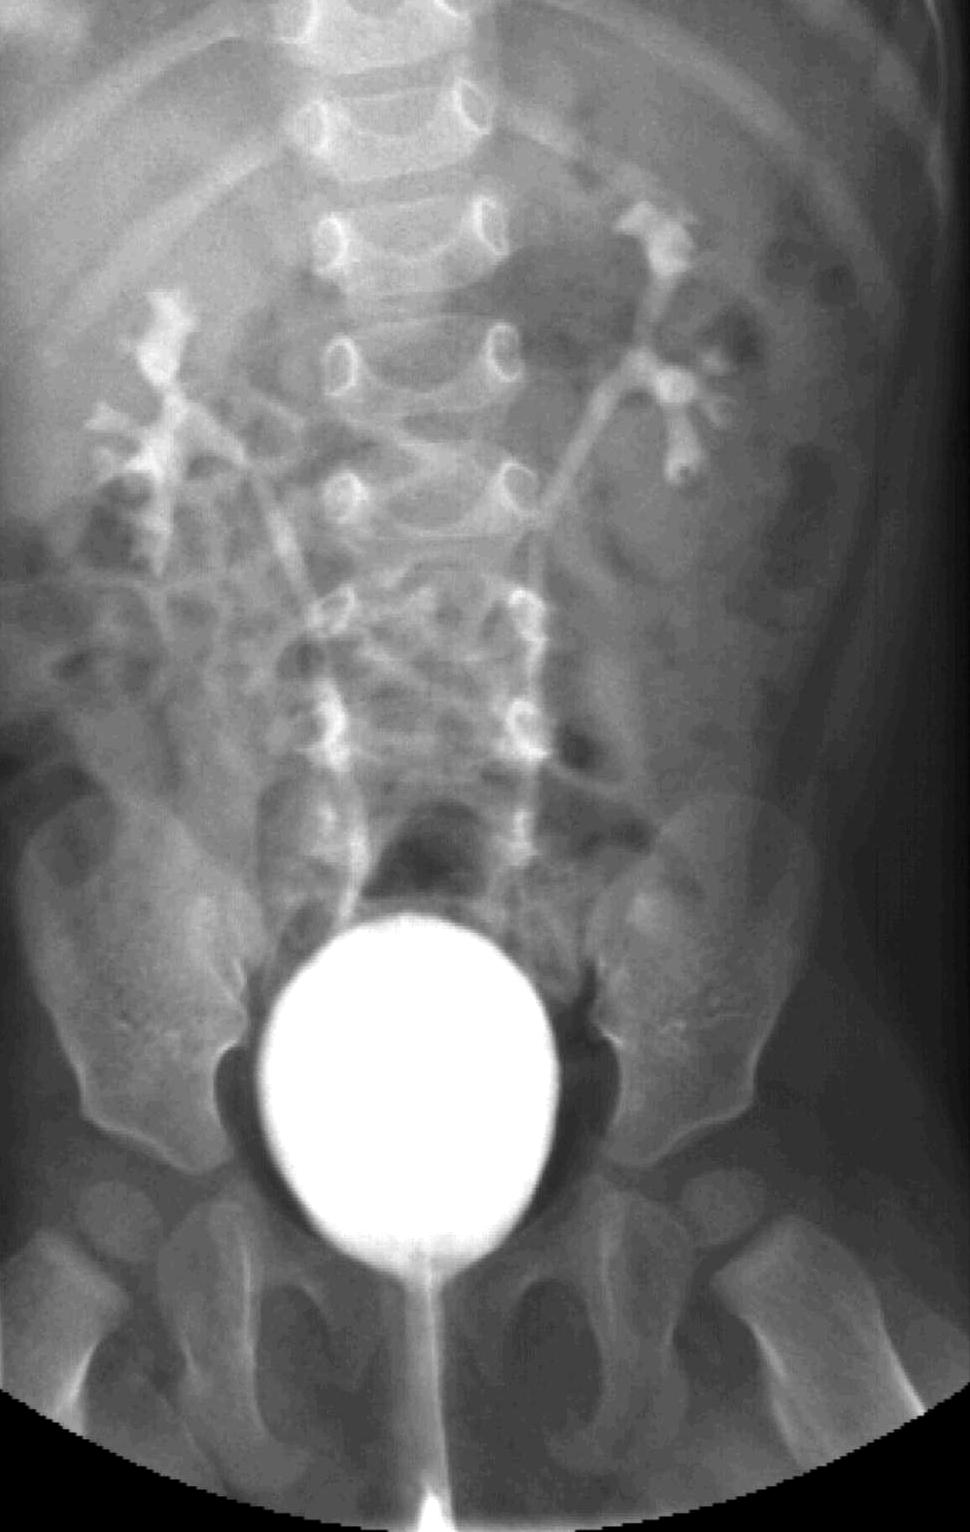

Necrotizing enterocolitis (NEC). It is a severe intestinal necrotizing disease of the newborns. It usually occurs as early as the first 10 days of life, but can happen in the first few months after birth. Vomiting, distended intestines, bloody stool, acidosis, peritonitis and perforation are frequent findings. Plain abdominal X-ray can be non-informative in the early stages of the disease; later distension indicates the separation of loops due to wall thickening. Often, air bubbles appear in the intestinal subserosal or submocosal layers, as characteristic signs of “intestinal pneumatosis”. The intramural air can diffuse to the mesenteric veins and appear in the portal circulation in the projection of the liver. Free abdominal air is indicative of perforation and requires surgical intervention. US examination can reveal these characteristics of the disease before X-ray is indicative. US can depict thickened intestinal wall, portal and intramural air, abdominal free fluid or abscesses.

20. NEC, US examination. Free abdominal fluid, with dense inner echos. Air bullbles in the intestinal wall: “zebra” sign (arrow).